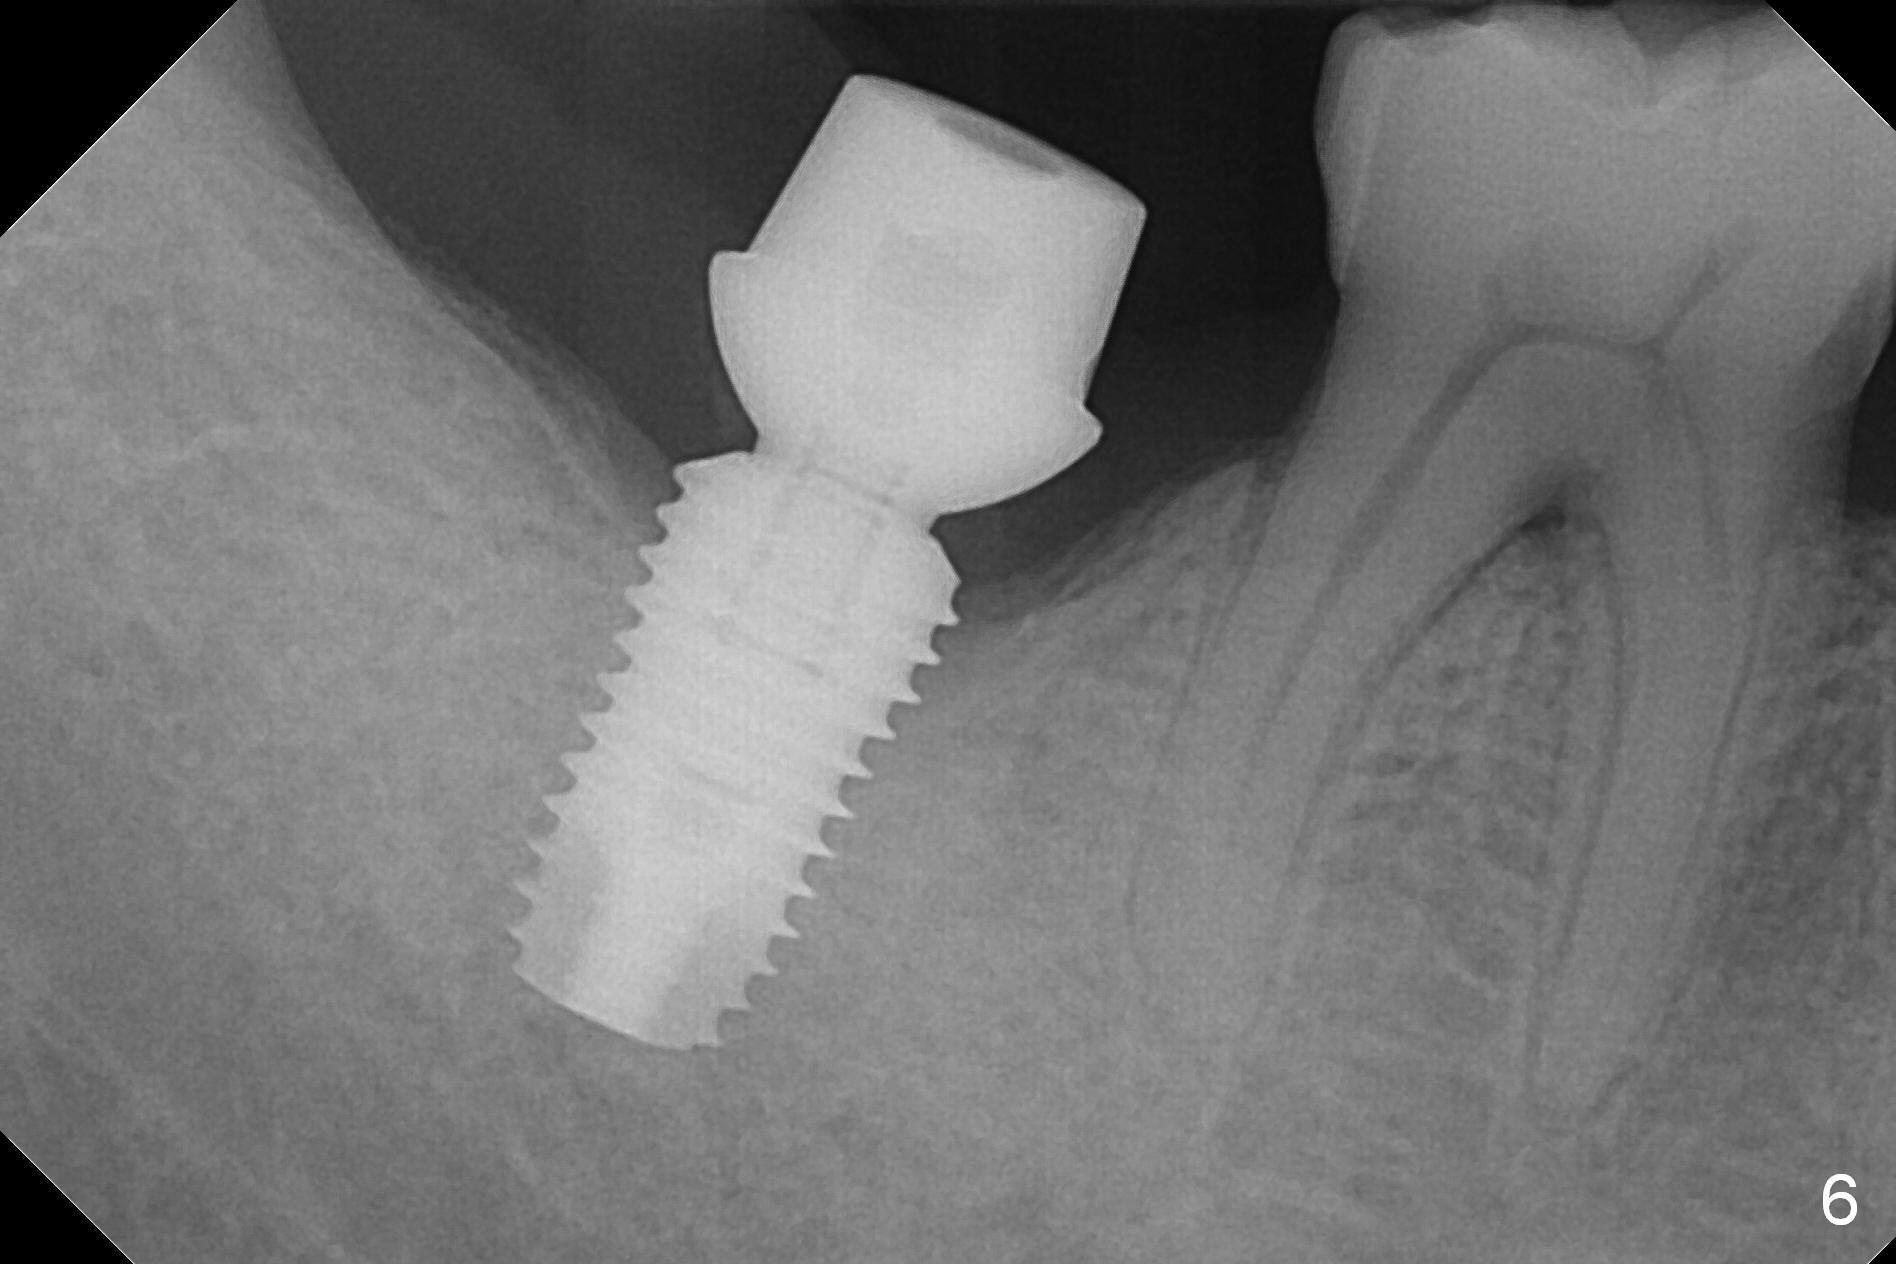

The implant appears to have osteointegrated 8 months postop (Fig.6). The bone loss is minimal 1 year 3 months post cementation (Fig.7) and 1 year 10 months post cementation (Fig.8).